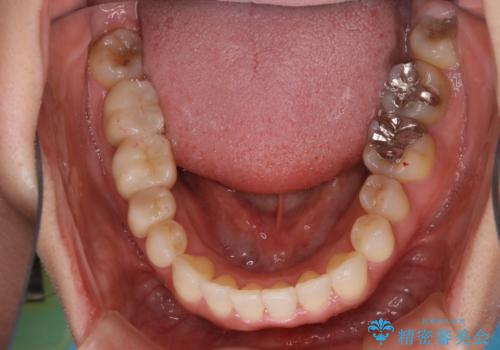

- 前歯のがたつきと反対咬合を主訴に来院されました。

インビザライン・クリンチェック(歯のシミュレーション)を行い、

インビザラインライトで治せる範囲であることを確認し治療を開始することになりました。

今回はクリンチェックを作成したのちに、枚数が少なくても可能であることが判明したためインビザラインライトでの治療を行いました。

最初はインビザラインモデレートパッケージの予定で契約をされていたので、金額も10万円以上安くなり仕上がりも満足頂きました。